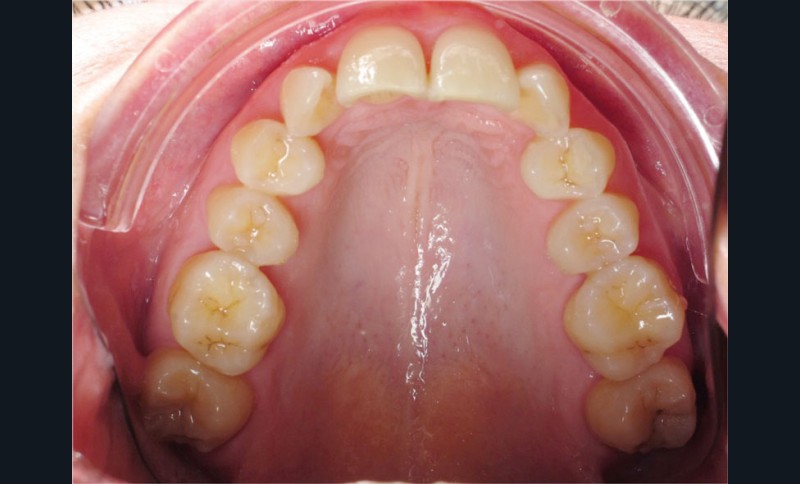

Cas n° 2

Nous lui avons donc proposé un traitement d’alignement avec maintien des 14 et 24 en position de 13 et 23 et optimisation du torque pour favoriser un développement des arcades et chercher à améliorer le sourire et le soutien labial.

Un appareillage Damon métal a été mis en place, réalisé à partir d’un set up numérique Insignia pour obtenir un contrôle précis des torques et de la forme d’arcade et réduire le temps de finition grâce à un collage indirect très précis.

De larges surélévations postérieures étalées ont été mises en place et la patiente a porté des élastiques précoces suivant les principes de la technique Damon. Les 14 et 24 rempliront le rôle des 13 et 23.

Les objectifs de traitement ont été remplis. Nous avons observé un excellent contrôle du torque et une absence de perte de l’occlusion postérieure grâce à la technique Insignia.